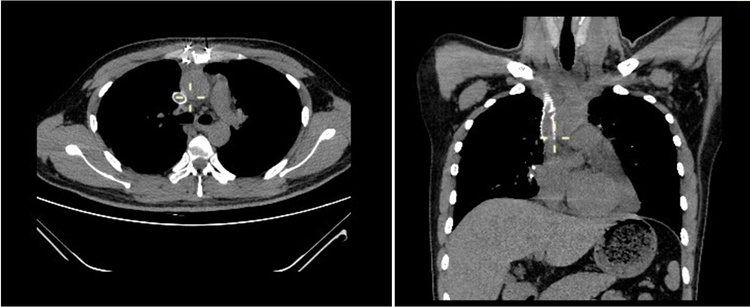

手术完成后,患者进入重症监护病房,在医护人员的严密监护和治疗下,辅助予针灸理疗等中医康复手段,莫先生克服了术后重症肌无力危象和肺部感染等可能出现的并发症,逐渐康复并恢复了年轻人的活力,顺利出院。复查胸部CT纵隔内未见明显肿瘤性占位病变,人工血管位置良好。

图3:术后复查胸部CT情况。